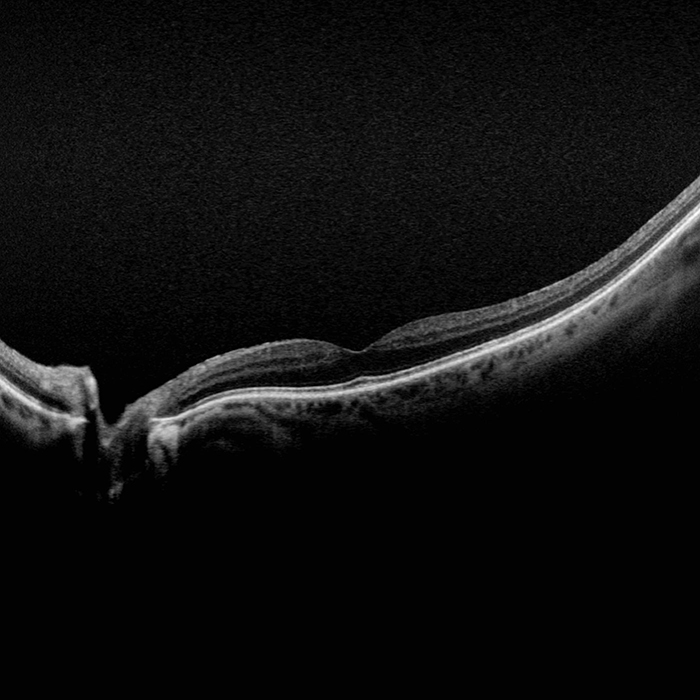

MonacoPro provides an exciting new way to enhance your clinical exam. The only ultra-widefield retinal imaging device with integrated Spectral Domain OCT, MonacoPro produces a 200° single shot optomap image in less than ½ second and also provides cross-sectional 40° OCT views of retinal structures. Engineered for efficiency, MonacoPro captures up to five imaging modalities for both eyes in just 90 seconds, optimizing workflow, streamlining diagnostics, and delivering superior patient care.

Spectral Domain Optical Coherence Tomography (OCT)

Typical Axial Resolution: <7 micron (in tissue) Digital on-screen <5 micron

Transverse Resolution: <20 micron (in tissue), Digital on-screen <15 micron

Scan Depth: 2.3 mm (in tissue)

Spectral Domain OCT

A-Scan rate up to 70k cycles/s